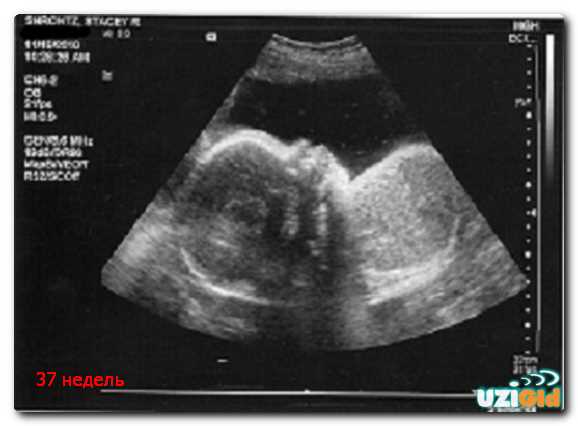

Нормальные показатели веса на 37 неделе

На данном этапе развития, параметры могут варьироваться, и обычный диапазон составляет от 2,5 до 3,5 килограммов. Следует учитывать, что индивидуальные особенности матери и наследственность играют значительную роль в формировании этих значений.

Методы оценки веса на УЗИ

Разные подходы позволяют получить более точное представление о массе ребенка на УЗИ. Наиболее распространенные методы включают:

- Метод Флеминга – основан на измерении окружности живота и длины бедренной кости. Формула позволяет приблизительно рассчитать массу, учитывая эти параметры.

- Метод Кратцера – использует параметры окружности головы, объема живота и длины бедренной кости для более точной оценки. Этот подход часто считается более надежным при наличии всех необходимых измерений.

- Модели математической регрессии – алгоритмы, которые учитывают множество факторов, таких как анатомические размеры и пол. Эти модели способны учитывать индивидуальные характеристики.

- Определение по графикам роста – анализирует результаты предыдущих УЗИ. Сравнение текущих параметров с эталонными значениями помогает спрогнозировать массу.

При проведении обследования важно учитывать квалификацию специалиста и качество оборудования. Погрешность измерений может варьироваться, поэтому результаты следует интерпретировать с учетом контекста.

Сравнение результатов с предыдущими обследованиями помогает понять динамику развития. Если есть сомнения в точности, можно провести дополнительные исследования для более детального анализа.